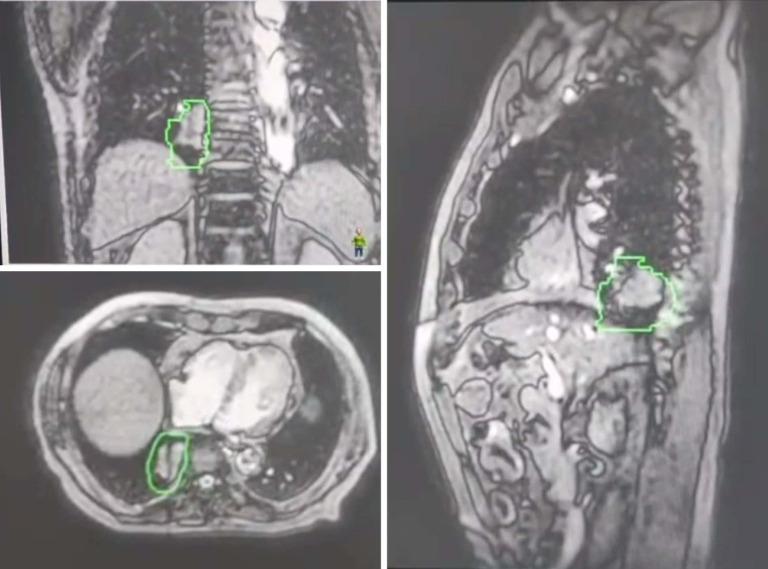

Stereotactic body radiotherapy (SBRT) is crucial for lung tumor treatment, but facing challenges like intra-fractional anatomical changes and organ risks. Magnetic resonance-guided online adaptive SBRT (MRg-SBRT) is an innovative technique promising safer delivery of ablative doses and protect organ at risk (OAR). This study aimed to investigate the feasibility of the whole process of MRg-SBRT for non-small cell lung cancer (NSCLC) patients.

Physical parameters of radiotherapy for 23 cases of NSCLC who underwent MRg-SBRT were retrospectively analyzed. This included patients' treatment course, planned target volume (PTV), target area coverage, and OAR recipient volume. The focus was on inter- and intra-fraction MR real-time monitoring to correct off-target. Local control and adverse event outcomes of patients' SBRT treatment were also retrospectively analyzed.

All 23 patients completed treatment on time without any treatment interruptions or pauses due to the MR. Tumor movement was predominantly in the superior-inferior (SI) directions through Elekta Unity real-time online monitoring. The baseline plan was altered in four patients, and an adaptive plan was used to correct inter- and intra-fraction off-targeting in a timely manner. The prescribed dose coverage for PTV was 95.3%, with a median bilateral lung volume 20 (V20) GY of 6.3%, and a maximal dose to the spinal cord of 117.3 cGy. The response results showed that the disease control rate (DCR) was 100% with an objective response rate (ORR) of 82.6%. Follow-up results showed an acute grade one to two pneumonia incidence of 82.6% and grade three pneumonias in one patient.

MRg-SBRT can guide treatment plans for the clinical needs of SBRT for lung cancer patients, especially for old patients, proving the feasibility of SBRT for lung lesions with MRg-SBRT, and online real-time monitoring reduces intra- and inter-fraction off-targeting, and guarantees the treatment efficiency of patients without significantly increasing the incidence of serious adverse events.